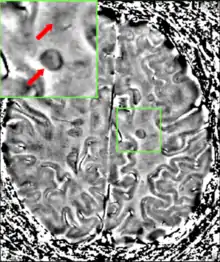

Specific, SM implică pierderea de oligodendrocite, celulele care creează și mențin un strat adipos — numit teacă de mielină — care ajută neuronii să transmită semnale electrice (potențiale de acțiune).[4] Consecința este subțierea sau dispariția completă a mielinei și, pe măsură ce boala progresează, distrugerea axonilor neuronali. În absența mielinei, neuronul nu mai poate transmite semnalele electrice.[5] Un proces de reparație, numit remielinizare, are loc în fazele incipiente ale bolii, însă oligodendrocitele nu pot să reconstituie integral teaca de mielină a celulei.[34] Crizele repetate duc la remielinizări din ce în ce mai deficitare, până când în jurul axonilor afectați se formează o placă asemănătoare unei cicatrice.[34] Aceste cicatrice sunt originea simptomelor; testele efectuate cu imagistică prin rezonanță magnetică (RMN) arată că în timpul unei crize se formează frecvent mai mult de zece noi plăci.[4] Acest fapt ar putea sugera că există un număr de leziuni până la care creierul se poate repara fără a produce consecințe vizibile.[4] Un alt proces implicat în apariția leziunilor este creșterea numărului de astrocite la valori anormale, din cauza distrugerii neuronilor învecinați.[4] Au fost descrise mai multe tipare ale leziunilor.[35]

Datele clinice pot fi suficiente pentru diagnosticarea SM dacă pacientul a prezentat în trecut episoade de simptomatologie neurologică specifică bolii.[38] La persoanele care se prezintă la medic după un singur episod, sunt necesare teste suplimentare pentru stabilirea diagnosticului. Cele mai frecvent utilizate metode de diagnostic sunt neuroimagistica, analiza lichidului cefalorahidian și potențialele evocate. Explorarea creierului și a măduvei spinale prin imagistică prin rezonanță magnetică poate indica zonele demielinizate (leziuni sau plăci). Se poate administra gadoliniu intravenos ca substanță de contrast pentru a evidenția plăcile active și pentru a demonstra, prin eliminare, existența unor leziuni anterioare neasociate cu simptomele prezentate în momentul evaluării.[38][40] Examinarea lichidului cefalorahidian prelevat prin puncție lombară poate oferi dovezi ale existenței unei inflamații cronice în sistemul nervos central. Lichidul cefalorahidian este examinat pentru a se decela benzi oligoclonale de IgG la electroforeză, acestea fiind markeri ai inflamației prezenți la 75–85% din persoanele afectate de SM.[38][41] Este posibil ca sistemul nervos afectat de SM să aibă un răspuns mai puțin activ la stimularea nervului optic și a nervilor senzitivi din cauza demielinizării acestor traiecte nervoase. Reacțiile creierului pot fi examinate vizual și prin potențialele evocate senzitive.[42]